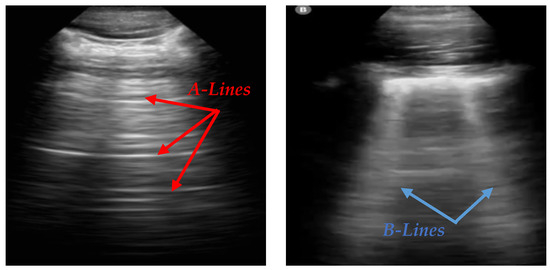

Lung POCUS shows different ultrasound patterns in COVID-19 compared to pulmonary edema, bacterial pneumonia, and other viral pneumonias, and is thus useful in differentiating between these conditions [2]. In LUS, A-lines and B-lines serve as crucial markers in the evaluation of lung health. A-lines are horizontal, reverberation artifacts seen in healthy, aerated lung tissue. These lines are typically observed when there is no abnormal fluid accumulation in the lungs, indicating normal lung conditions. B-lines are vertical, hyperechoic artifacts that extend from the pleural line to the bottom of the ultrasound image, often seen in pathological conditions. The presence of B-lines can indicate interstitial lung disease, pulmonary edema, or lung infections such as COVID-19 [3]. Various tools, like ExoLungAI, have been developed to detect these artifacts in ultrasound videos, categorizing them based on the quantity of A-lines and B-lines. Videos with more than five B-lines are classified as B-line cases, while those with dominant A-lines fall into a separate category [4]. Figure 1 illustrates the appearance of A-lines and B-lines in the lung ultrasound images used in this study.

Figure 1. An illustration of A-lines and B-lines in an LUS image. A-lines are horizontal reverberation artifacts indicating normal aerated lung tissue, while B-lines are vertical, hyperechoic artifacts extending from the pleural line to the edge of the image, signifying potential lung abnormalities [5].